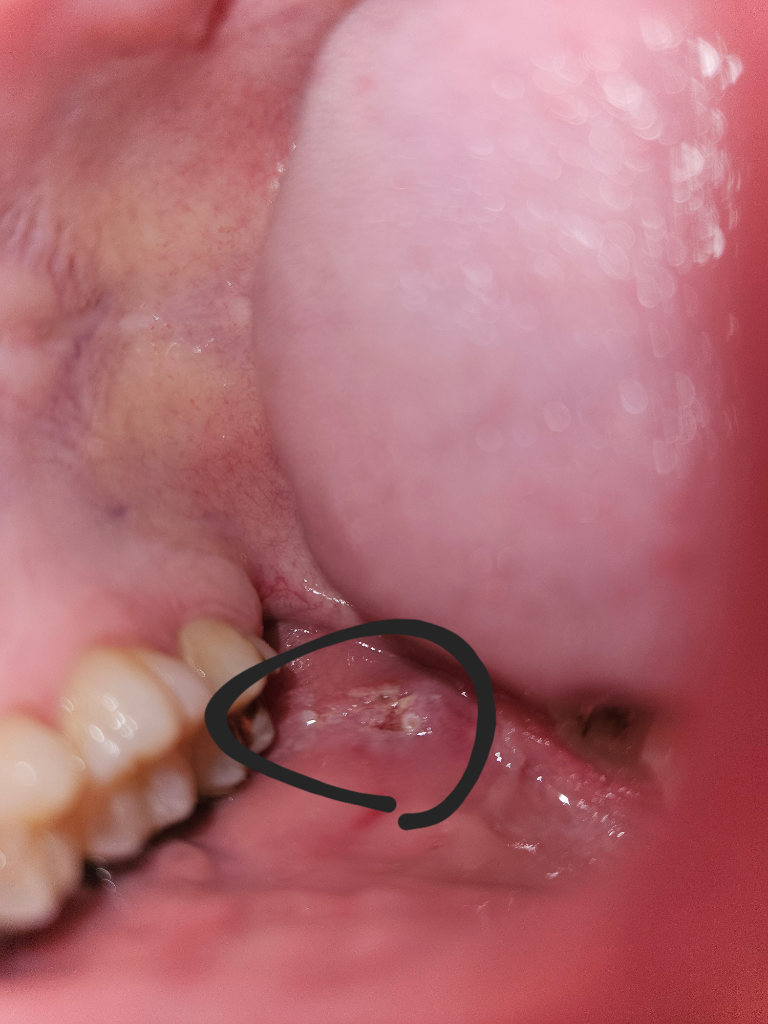

현재 치아 교정 중입니다. 두 달 전 식사를 하던 중 교정기 철사가 왼쪽 볼을 찌르며 볼살에 낀적이 있는데 그때는 상처가 없었던것같고 후에 치과 방문 후 철사가 볼을 찌르지 않도록 조치 하였습니다. 그 후 따로 아픈적은 없었던거같은데 대략 2주 전 그때 찔렸던 왼쪽 볼에 상처가 났으며 상처 부위에 음식을 씹으며 치아가 닿거나 양치를 하는 등 무언가 닿게 되면 아프고 무언가 닿지 않으면 별 다른 느낌이 없습니다. 그냥 단순히 교정기가 쓸려 난 상처인가요? 아니면 다른 병이나 그런게 있는 건가요 병원은 이번주 방문이 힘들어 다음주 토요일 27일에 치과 방문이 예약되어 있어 그때 방문할까 합니다.아래 사진 첨부합니다.

입안에 염증이 생긴 것으로 보이며, 이 경우 소독을 위해 헥사메딘 가글액으로 가글하고, 구내염 연고 사용을 하며 상태를 지켜보길 권합니다.

양상은 외상성궤양이고 위치상 교정 철사의 찔림으로 그런것 같습니다 구강내 적용가능한 연고를 바르면 도움이 됩니다